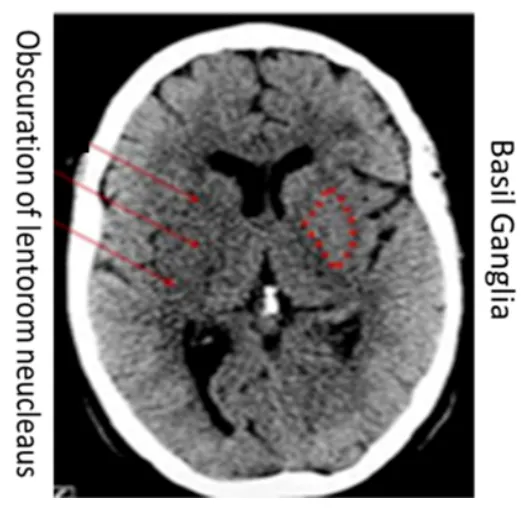

(2) Gray matter 와 wihte matter 경계가 불분명

(해설) 뇌경색의 비교적 초기에 나타날 수 있는 현상으로서, 경색이 발생한 부위에 Grey matter와 White matter의 경계가 모호해지는 것입니다.

우측 사진의 기저핵 (Basal ganglia)부위를 보면, 좌측 뇌에서는 백질과 회백질의 경계가 뚜렷하지만, 경색이 발생한 우츨에서는 그 경계가 모호해진 것을 볼 수 있습니다.